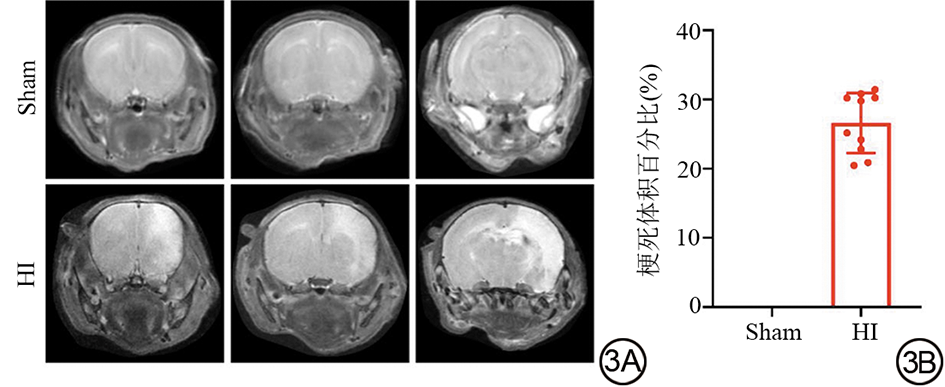

纵向体质量监测显示,与Sham组相比,HI组大鼠术后体质量增长率降低(0.954±0.157,P<0.05)。动态变化曲线表明,HI组体质量增长自术后早期即持续落后;事后分析发现,术后第1、3天两组差异无统计学意义,直至第7天,HI组体质量低于Sham组[(24.000±2.383) g vs.​(25.889±1.244) g,P<0.05],具体结果见图2。术后24 h脑部T2WI显示,HI组右侧大脑半球出现弥漫性T2高信号,而Sham组结构正常、信号均匀。梗死体积定量分析证实,HI组梗死百分比(26.60%±4.34%)高于Sham组(P<0.001)。​以上从生理发育到脑部结构的综合评估表明,HI手术成功构建了兼具生长发育障碍与明确结构性脑损伤的动物模型,详见图3

图3  HI后新生大鼠脑损伤及梗死体积定量分析。​​​​3A:术后24 h Sham组与HI组脑部冠状位T2WI代表性图像。Sham组脑组织信号均匀、结构完整;HI组患侧大脑半球可见明显T2高信号,提示广泛脑水肿及梗死。3B:梗死体积定量分析。T2WI:T2加权成像;HI:缺氧缺血性脑损伤;Sham:假手术。

Fig. 3  Quantitative analysis of brain damage and infarct volume in neonatal rats after HI. 3A: Representative coronal T2WI images of the brain from Sham and HI groups at 24 h post-surgery. The Sham group showed uniform signal intensity and intact structure; the HI group exhibited marked T2 hyperintensity in the affected cerebral hemisphere, indicating extensive brain edema and infarction. 3B: Quantitative analysis of infarct volume. T2WI: T2-weighted imaging; HI: Hypoxic-Ischemic brain injury; Sham: Sham operation.